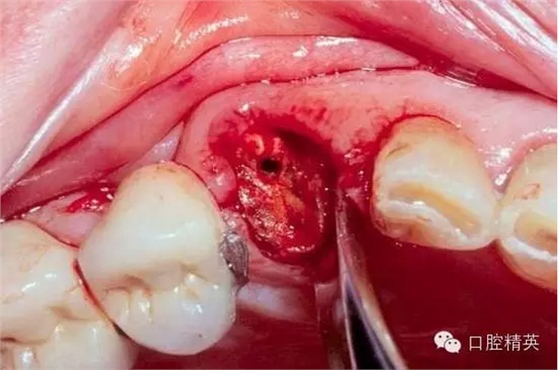

可以看到,luxator因為很薄的刃,能很容易插入牙周膜根向,從而獲得更穩(wěn)定的支點和更長的動力臂,不需要我們敲錘增隙,更不用去骨,從而保留更多的骨板。

拔除后軟硬組織的創(chuàng)傷都很小。